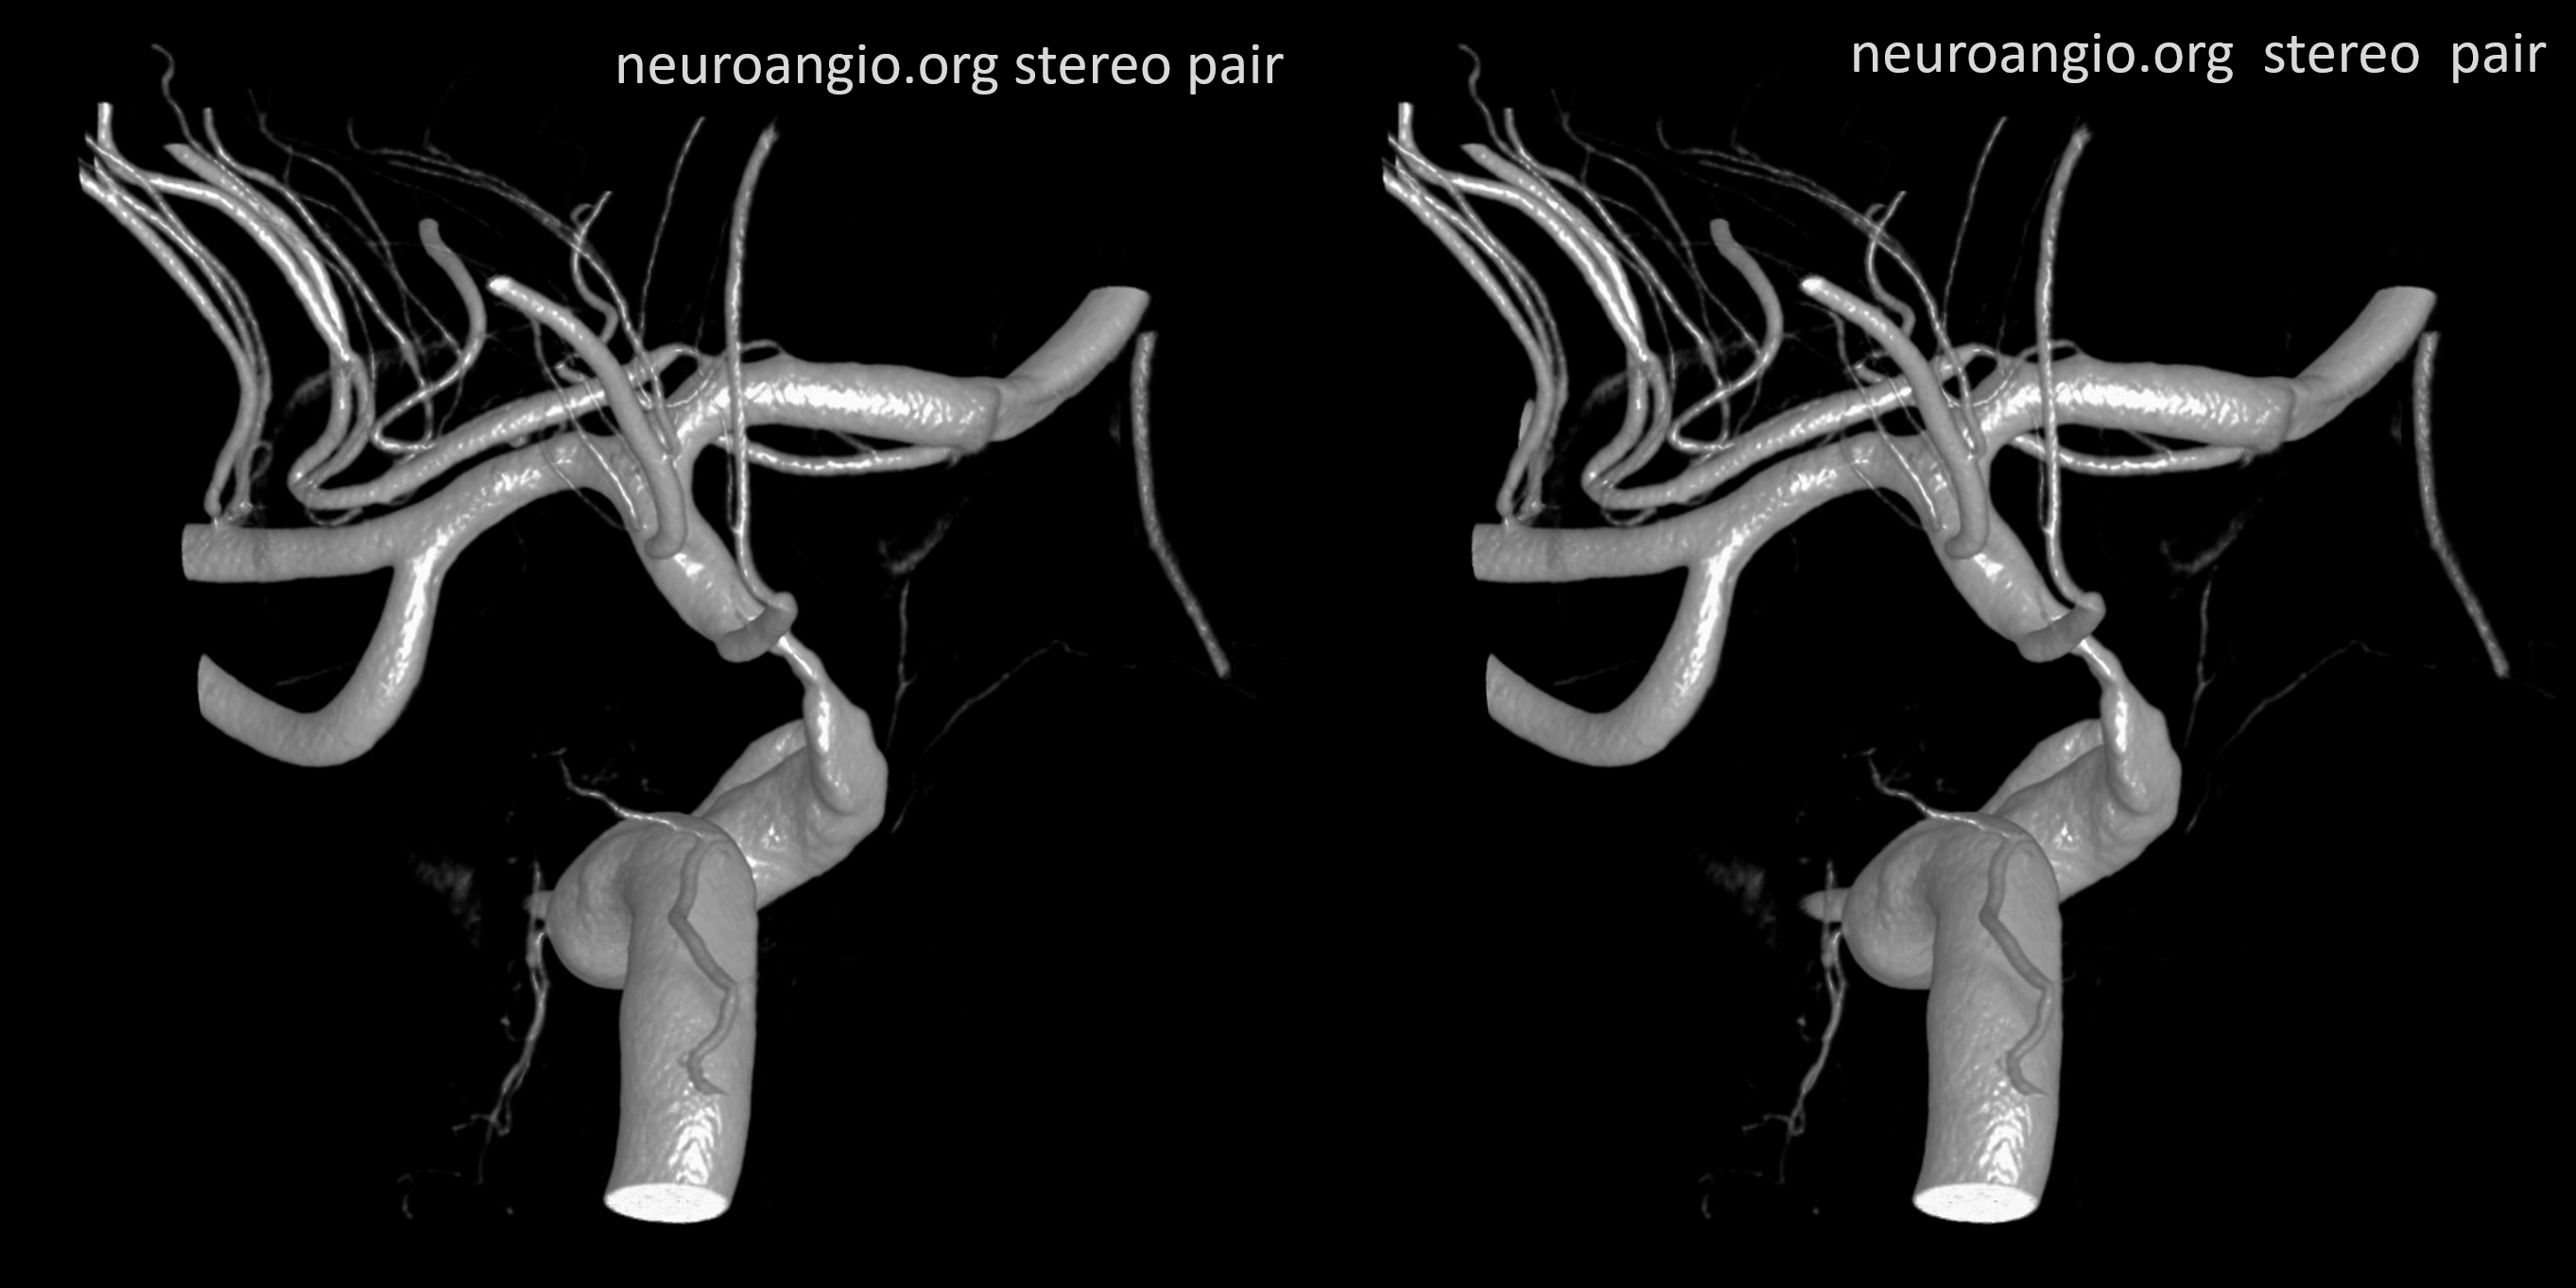

Stereos and MIPs. Both superior and inferior hypophyseals are well seen. The superior hypophyseal, despite being invisible on standard issue views, is quite large, even having two branches to the hypophysis.

Case courtesy Dr. Eytan Raz — here is a beautiful example of a very dominant superior hypophyseal artery (arrow) supplying the posterior hypophysis (arrowhead), with a correspondingly small inferior hypophyseal contribution from the MHT (dashed arrow)

Cross eye stereo

View from the back — again small inferior hypophyseal, big superior hypophyseal — balance again… See the beautiful vascular ring of the posterior pituitary — the connecting it with the contralateral side

Cross-eye stereo

MIP image shows the sella nicely — and helps prove its posterior pituitary

Pure arrowless images — easier to steal…

Of course, there is an aneurysm here — the branch point camp would point out how this larger than usual branch is a setup for aneurysmal formation. Naturally…